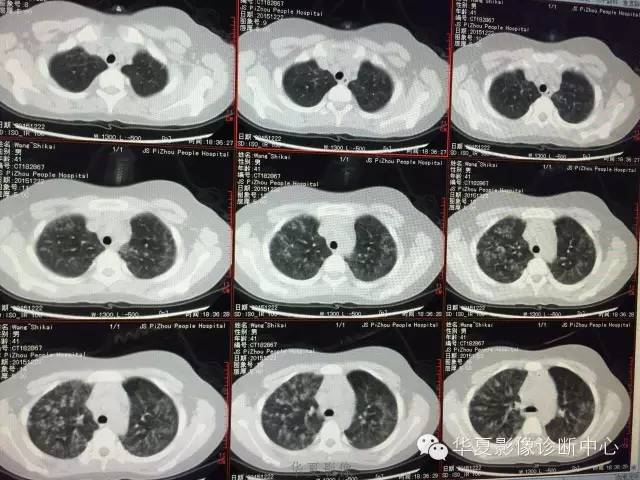

支原体肺炎1例CT影像表现

【病例】支原体肺炎1例CT影像表现